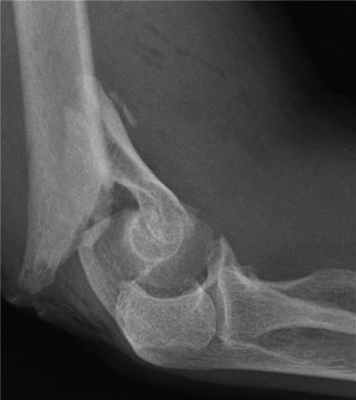

Пациентка с тяжелым внутрисуставным переломом нижнего отдела (мыщелков) плечевой кости с тяжелым повреждением локтевого сустава.

Рентгенограмма до операции.

Выполнена операция: металлоостеосинтез плечевой кости современными пластинами LCP, анатомия локтевого сустава полностью восстановлена.

Гипсовая повязка после операции не применялась, сразу разрешена разработка движений в суставах конечности. Результат через 5 дней после операции. Швы еще не сняты, виден отек, кровоподтеки на конечности после перелома. Уже видна хорошая функция конечности.

Результат через 3 мес. после операции. Функция конечности полностью восстановлена.